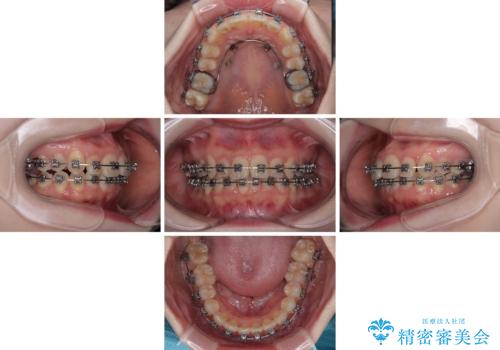

- メタルブラケット

- 1年11ヶ月

- 上下前歯のデコボコを気にして来院された患者様です。

マウスピースでもワイヤー装置でも対応可能でしたが、右側の咬み合わせが上顎がやや前方に位置していることから、補助装置を使用することが推奨されました。

自己管理の煩わしさを気にして、補助装置併用によるワイヤー装置での矯正治療を行うこととしました。